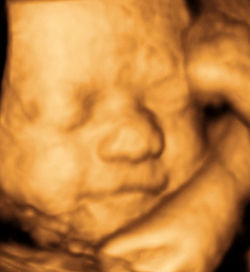

Your first 3D4D view of your unborn child will take place in our charming and comfortable exam rooms performed by highly trained sonographers under the guidance and medical supervision of our Board Certified Obstetricians. Salinas 3D/4D uses the most technologically advanced 2D/3D/4D ultrasound equipment in the market. Our friendly and knowledgeable office staff is committed to making this a truly enjoyable and memorable experience for you.

Finally, a comprehensive obstetrical ultrasound that provides expectant mothers with a complete package of fetal evaluation and 3D & 4D (live motion) images of your baby.

Salinas 3D4D is a subsidiary of Ob-Gyn Associates of the Central Coast, a Medical Corporation owned by Board Certified Obstetricians who are members of the American Institue of Ultrasound Examination (AIUM). It is our desire to provide you with not only a fun, educational and exhilarating bonding experience with your unborn child, but also provide you with the assurances of a healthy pregnancy that can only be delivered with a complete diagnostic ultrasound examination. We take pride in using the latest medical technology for medical purposes and do not promote keepsake-only ultrasound.